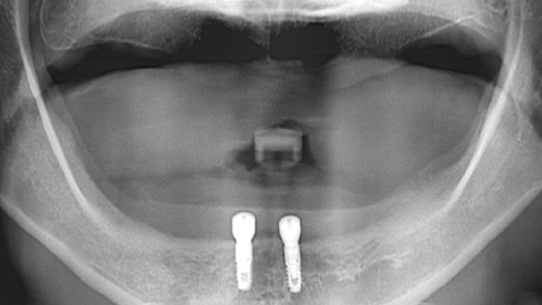

틀니가 번번히 탈락되어 일상생활이 불편하셔서 내원, 고정력이 없는 틀니를 사용하여 잇몸 염증과 통증 있으셨습니다. 상악의 경우 틀니를 오랫동안 착용하여 잇몸 뼈 소실이 심해 일반 틀니를 제작하고, 하악의 경우 임플란트 2개를 식립 후 임플란트 틀니를 제작해 드렸습니다.

하악에 임플란트 2개 식립